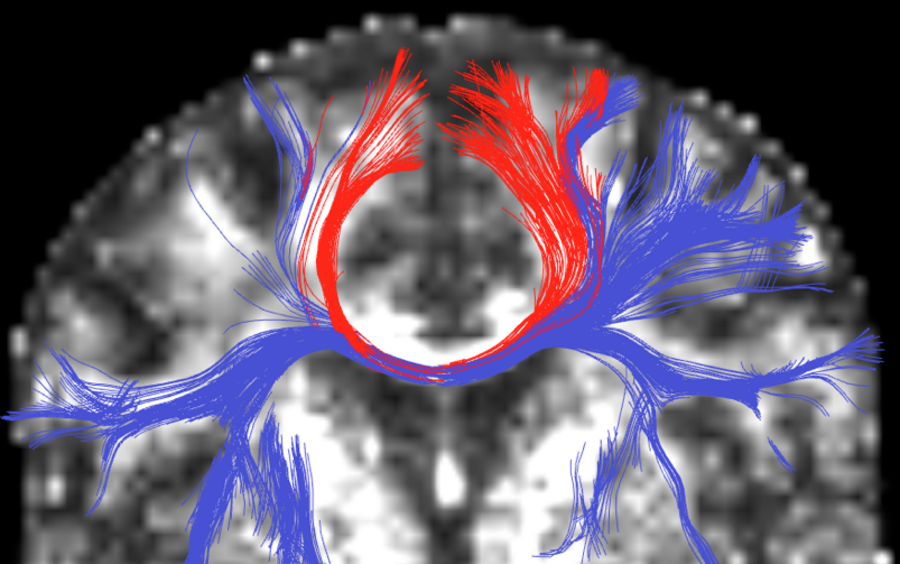

Multiple Fiber Model Tractography

Image legend: Multiple fiber model tractography using unscented Kalman filtering. Note the additional tracts (blue) the new method finds.

The White Matter Architecture Core has developed tractography methods that can trace complex white matter regions, such as regions where there is heavy crossing and branching of the fiber tracts [Malcolm, 2009]. In this work we propose a technique to simultaneously estimate the local fiber orientations and perform multi-fiber tractography. Existing techniques estimate the local fiber orientation at each voxel independently. Consequently, there is no running knowledge of confidence in the measured signal or estimated fiber orientation. Further, to overcome noise, many algorithms use a filter as a post-processing step to obtain a smooth trajectory. Fiber tracking is formulated as a causal estimation: at each step of tracing the fiber, the current estimate of the signal is guided by the previous. The signal is modeled as a discrete mixture of Watson directional functions, and the tractography is performed within a filtering framework. Starting from a seed point, each fiber is traced to its termination using an unscented Kalman filter to simultaneously fit the signal and propagate in the most consistent direction. Despite the presence of noise and uncertainty, this provides an accurate estimate of the local structure at each point along the fiber. The Watson function was chosen since it provides a compact representation of the signal parameterized by the principal diffusion direction and a scaling parameter describing anisotropy. It also allows analytic reconstruction of the oriented diffusion function from those parameters. Using a mixture of two and three components (corresponding to two-fiber and three-fiber models) we demonstrate in synthetic experiments that this approach reduces signal reconstruction error and significantly improves the angular resolution at crossings and branchings. In vivo experiments shown in the figure examine the corpus callosum and internal capsule and confirm the ability to trace through regions known to contain such crossing and branching while providing inherent path regularization.